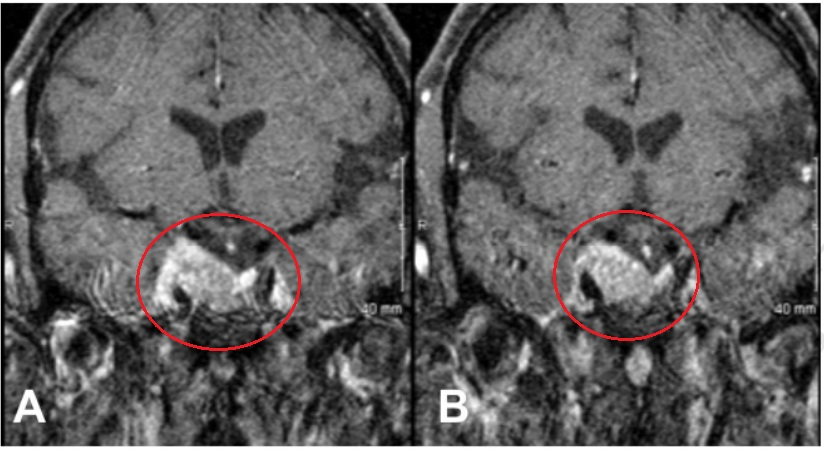

53岁男性患者,7年前在外院手术切除2级脑膜瘤。因出现三叉神经V1、V2区麻木,V3感觉迟钝入院。MRI见巨大脑膜瘤复发侵犯右侧海绵窦、眶顶、SphS、PPF和ITF并通过Meckel’s腔(MC)延伸至小脑桥脑角(CPA)(图 a-c)。

采用原额颞入路,显微镜+神经内镜-“双镜联合”,术后MRI显示肿瘤全切除。

术前术后影像对比:(A)术前MRI显示脑膜瘤延伸至后颅窝(PF)、海绵窦(CS)、眼眶和蝶窦(SS)。(B)肿瘤延伸至中窝、翼腭窝(PPF)和颞下窝(ITF)。(C)术前CT显示更大的蝶翼侵蚀和SS受累。(D, E)术后MRI显示肿瘤完全切除。(F)术后轴位CT扫描显示用于闭合的脂肪移植物。